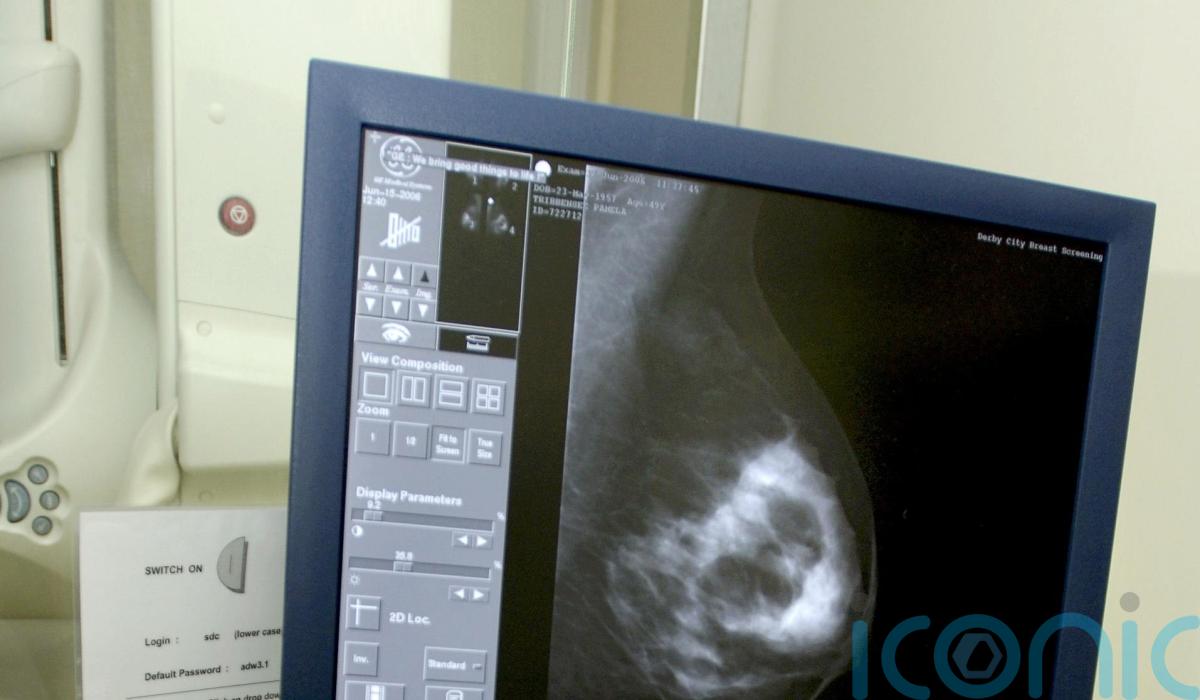

Breast cancer spreads at night, new research suggests

Breast cancer spreads most while patients are sleeping, new research suggests.

According to the World Health Organisation (WHO), breast cancer is one of the most common forms of cancer, and each year around 2.3 million people worldwide contract the disease.